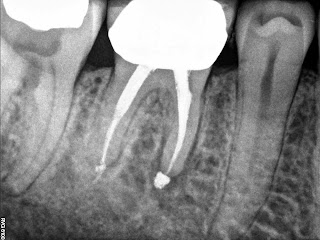

Root Canal Lower Molar First – 65 WM Posted on September 10, 2012February 27, 2026 by Bryan Root Canal Lower Molar First Normal anatomy Check out these other posts you may enjoy! Root canal anatomy maxillary premolar Selective Root Retreatment First permanent molar FPM extraction Master Apical Size Leave a ReplyYour email address will not be published. Required fields are marked *Comment * Name * Email * Website Δ